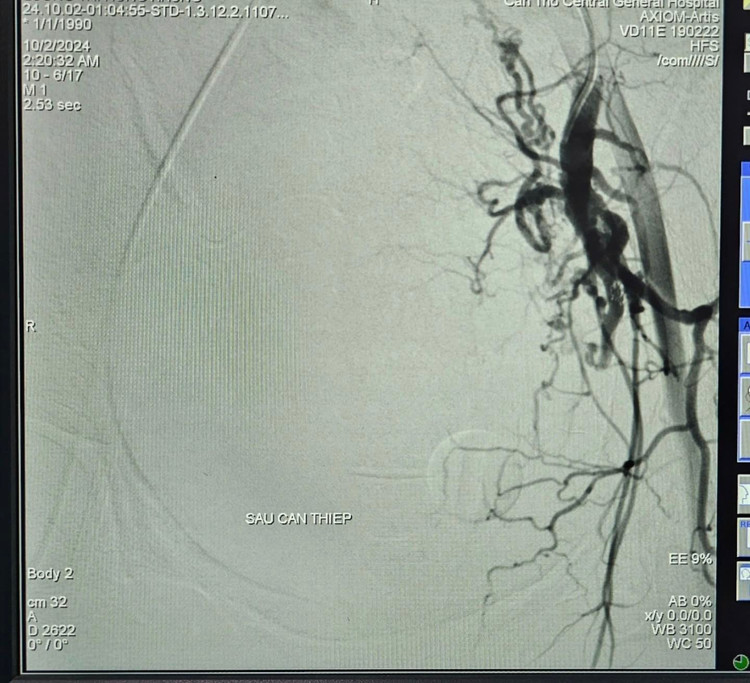

BS.CKII. Trần Công Khánh, Phó khoa Chẩn đoán hình ảnh và ê-kíp thực hiện, kết quả ghi nhận tăng sinh nhiều nhánh động mạch chậu trong hai bên, tổn thương co thắt mạch kèm ổ thoát thuốc vùng tiểu khung được cấp máu từ nhánh chậu trong trái, xác định vị trí và tiến hành bơm tắc bằng hỗn hợp keo, chụp kiểm tra ghi nhận không còn ổ thoát mạch, sinh hiệu bệnh nhân ổn định được chuyển khoa Hồi sức tích cực – Chống độc tiếp tục theo dõi.

Trưa ngày 02/10/2024, bệnh nhân có dấu hiệu xuất huyết nội tái phát và được chỉ định chụp cắt lớp vi tính bụng có cản quang kiểm tra phát hiện ổ thoát mạch, các bác sĩ tiến hành chụp và nút mạch điều trị cầm máu các tạng số hóa xóa nền (DSA) lần thứ hai. Kết quả ghi nhận hình ảnh thoát mạch được cấp máu từ nhánh động mạch mạc treo tràng trên, xác định vị trí tiến hành bơm tắc bằng hỗn hợp keo, thủ thuật tiến hành 40 phút, bệnh nhân ổn định tiếp tục hồi sức tích cực.

BS.CKII. Trần Công Khánh cho biết thêm ưu thế nổi bật của phương pháp nút mạch cầm máu điều trị chấn thương nội tạng là bảo tồn tối đa cơ quan nội tạng bị tổn thương, giúp bệnh nhân tránh được đại phẫu nặng nề, rút ngắn thời gian nằm viện và điều trị.